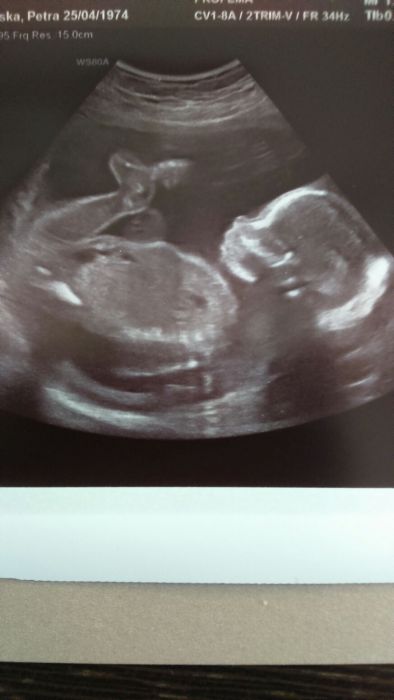

V úterý jsem byla na genetice ultrazvuku. Vše v pořádku. Holčička potvrzena. Jen mám stále dole placentu

Julča: Jé, taky hezký ufoun. A genetika je tedy ok? Já půjdu na další screening za tři týdny, už budu asi ve 21tt nebo tak nějak. Letí to jako blázen :-) A už jsi aspoň klidnější? A co ty pohyby, už ji cítíš? My pohlaví nevíme a ani nebudeme vědět :-)

Jééé, Julčo, gratulace ke genetice, a fotečka z utz nádherná.